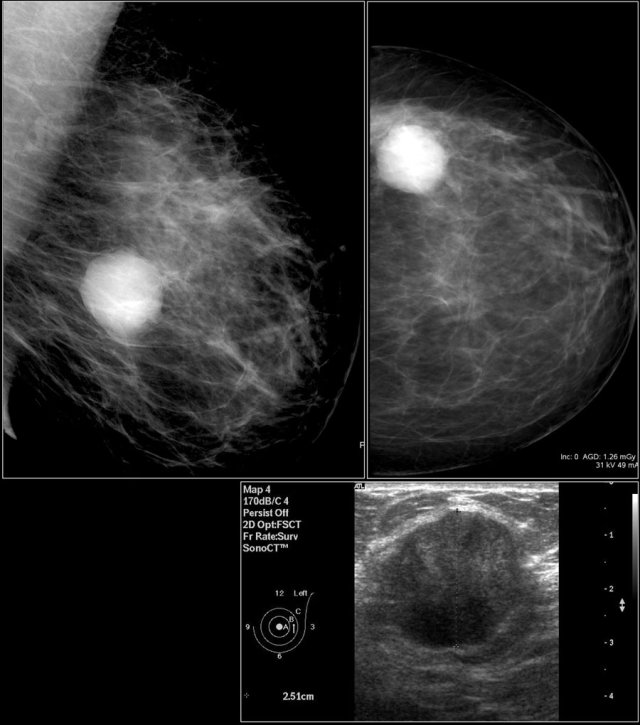

First study the images and describe the findings.

Then continue reading.

The findings are:

- Mass with irregular shape.

- Spiculated margin.

- High density.

- Ultrasound also shows irregular shape with indistinct margin.

This mass is categorized as BI-RADS 5.